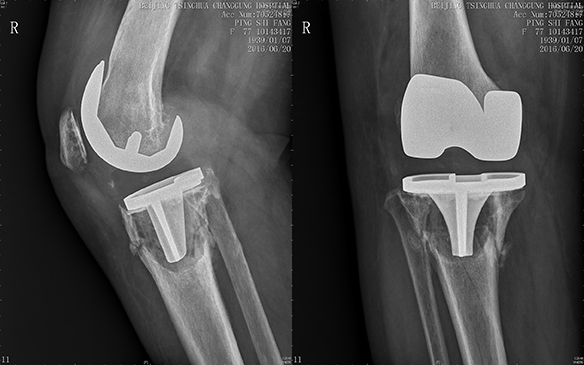

2016年6月29日,手术进行中,蔡谞教授在保留最大骨量的同时安全的将松动的假体和衬垫取出,同时进行彻底清创,将感染的风险降到最低,在面对几乎已经完全消失的胫骨平台,蔡谞教授选择使用骨小梁钽金属胫骨锥形填充块(CONE)起到支撑作用,在填充块内进行植骨以促进骨长入,同时在填充块和胫骨假体之间填充骨片,撑起胫骨假体。在关节中心团队以及手术室麻醉相关科室的合作下,手术历经3个多小时,完美收官。严重的骨缺损得到了良好的处理,翻修假体位置良好,患者术后第3天即可下地。

图为胫骨锥形填充块内填充异体骨